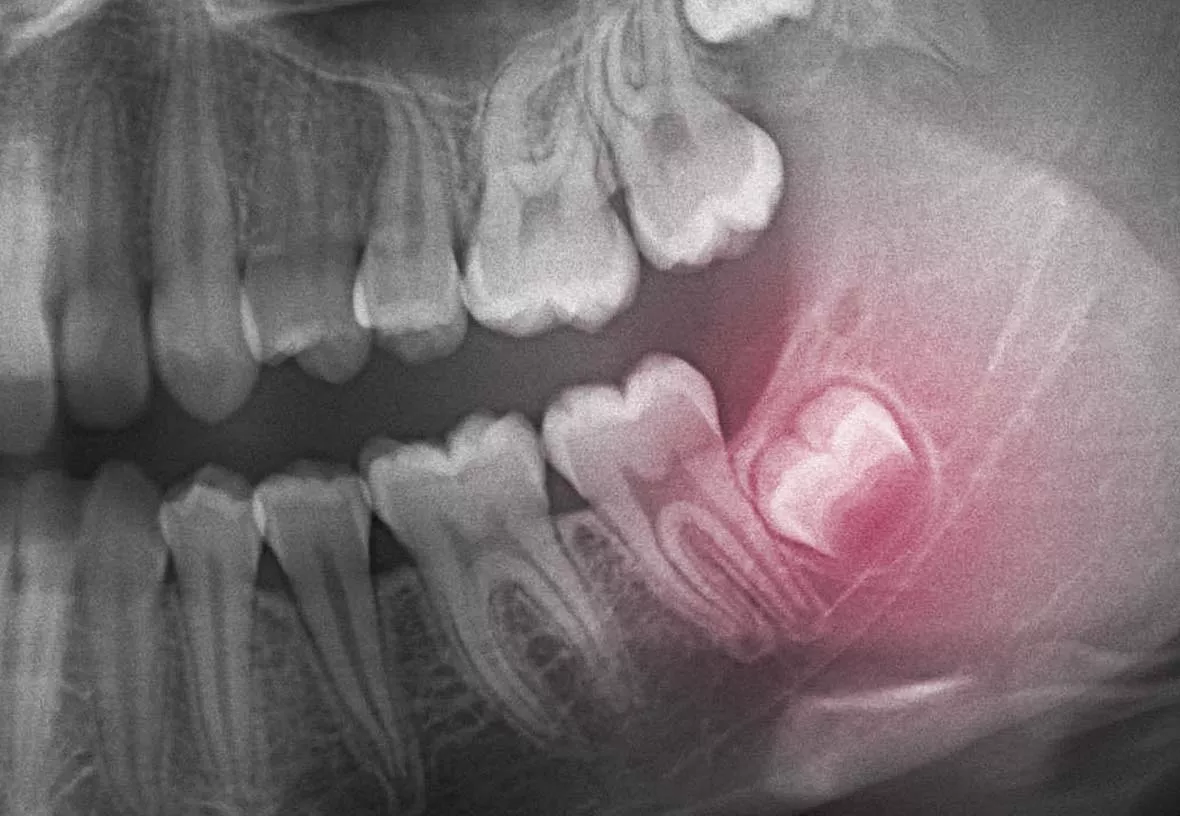

Your wisdom teeth are your last adult teeth. These large molars usually emerge behind your second set of molars at the back of your mouth. However, humans have evolved to have smaller jaws, and there is often not enough room in the jaw for the wisdom teeth to emerge correctly. When this happens, they can be crooked or grow under your other teeth and damage them. Your dentist will monitor the development of your wisdom teeth and recommend their extraction if they aren’t growing correctly.